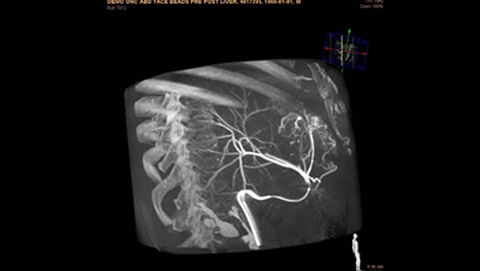

Live 3D MR/CT Roadmap fuses live 2D fluoroscopy on a pre-acquired MR or CT image, which may reveal hidden anomalies and enable real-time motion compensated navigation to support interventional procedures. Live 3D MR/CT Roadmap provides full 3D view for guidance of guidewires, catheters and coils through complex vessel and anatomical structures.

Dynamic 3D Roadmap provides a sustainable 3D roadmap to support interventional procedures. Dynamic 3D Roadmap matches the real-time 2D fluoroscopy images with the 3D-RA reconstruction of the vessel tree. It provides a 3D real-time insight of the advancement of the guide wire, catheter and coils through complex vessel structures. The Unsubtracted 3D Roadmap option reduces subtraction artifacts caused by patient breathing and movements, providing a clear roadmap during abdominal and thoracic interventions.

Live 3D Roadmap allows you to follow the advancement of guidewires, catheters and coils in real-time. It automatically adapts in real-time to changes in C-arm angulation and rotation, table movement, field of view and source-image distance.

High-resolution 3D-RA vascular images or previously acquired 3D segmented MRA or CTA data is registered to the current patient position through a low X-ray dose 3D-RA scan, allowing ‘re-use’ of contrast and X-ray doses.